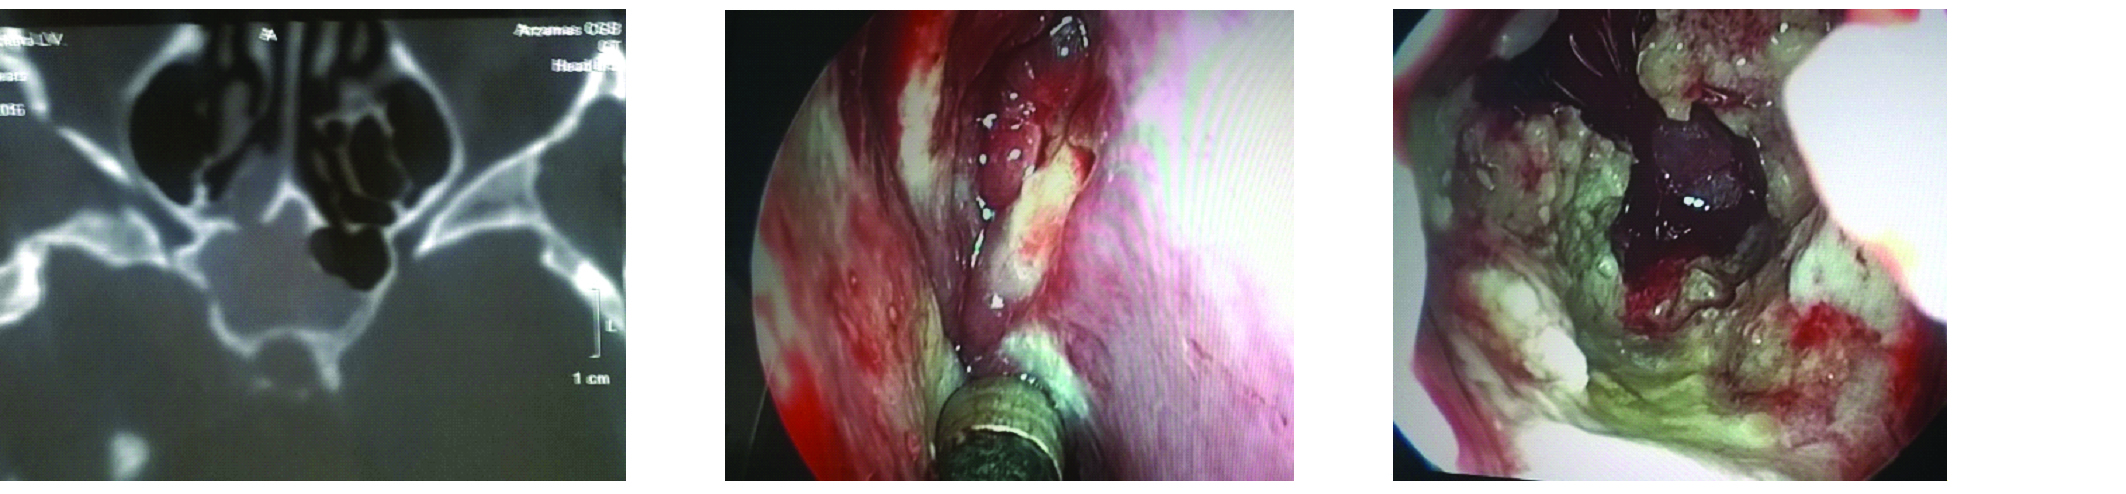

ВВЕДЕНИЕ В настоящее время в связи с распространением лучевых (МРТ, КТ) и визуальных (эндоскопия) методов диагностики наблюдается увеличение количества случаев изолированного сфеноидита [1, 2, 3]. Удельный вес изолированного сфеноидита в общей структуре заболеваний околоносовых пазух (ОНП), по данным литературы, составляет не более 5% [4, 5, 6]. Однако абсолютные цифры с учетом огромного количества случаев воспалительной патологии ОНП могут быть весьма значительными. В структуре синуситов все больше резистентных (устойчивых к лечению) форм, в том числе грибковых [7]. Данные о распространенности патологии весьма скудные, в структуре статистической отчетности стационаров и поликлиник сфеноидит как самостоятельная нозологическая форма отражается крайне редко. В то же время относительно невысокая распространенность нередко обусловливает пассивную позицию специалистов при дифференциальной диагностике поражений клиновидной пазухи (КП). Основное место в дифференциальной диагностике у данной группы пациентов занимают компьютерная томография (КТ) и магнитно-резонансная томография (МРТ). Однако трактовка результатов исследований не всегда однозначна и может приводить как к гипердиагностике, так и, наоборот, к гиподиагностике сфеноидита, выражающейся в недооценке данных лучевой диагностики и обьективной картины и нередко приводящей к развитию хронических и осложненных форм. Пациенты направляются к лор-врачу только после длительного, безуспешного лечения у специалистов смежных специальностей, что влечет высокий уровень гиподиагностики сфеноидита и наличие осложненных форм [8]. Дифференциальная диагностика патологического процесса в пазухе на дооперационном этапе чрезвычайно важна, поскольку необдуманное вмешательство может вызвать тяжелые и даже фатальные осложнения [9, 10]. От 5% до 30% всех изолированных поражений клиновидной пазухи составляют пациенты с неинвазивной грибковой формой [11, 12]. Для хронического сфеноидита характерно латентное (скрытое) течение, которое не всегда диагностируется на ранних стадиях [13, 14]. По данным ряда исследователей, частота патологических находок в клиновидной пазухе при аутопсии лиц, прижизненный диагноз «сфеноидит» у которых не был установлен, составляет от 10% до 68% [15, 16]. Очень важно изучение вопросов ремоделирования в клиновидной пазухе, в том числе явлений остеита при грибковых формах [17]. Осложненное течение изолированного сфеноиди-та - нередкое явление, при этом основным фактором развития осложнений является несвоевременная диагностика. Наиболее часто встречаются осложнения, связанные с вовлечением в патологический процесс глазодвигательных нервов, в особенности VI пары - n. abducens [4, 9, 16]. В литературе можно встретить наблюдения инвазивных, генерализованных форм грибкового сфеноидита с быстрым развитием офтальмологических, интракраниальных и системных (септических) осложнений [7, 12, 14]. Тактика лечения при изолированных поражениях клиновидной пазухи, по данным литературы, различная. Часть авторов считает наличие изолированного сфеноидита, особенно грибковых форм, мукоцеле, абсолютным показанием к операции. Другие авторы при отсутствии осложнений начинают с консервативной терапии [1, 3, 11, 12]. Задачей хирургического лечения у таких пациентов является не только купирование воспалительного процесса, но и создание условий для адекватной вентиляции пазух и предотвращения возможного рецидива. В то же время вопросы дифференцированного подхода к хирургическому лечению недостаточно освещены в научной литературе и носят преимущественно описательный характер. ш ЦЕЛЬ Провести анализ случаев изолированного поражения клиновидной пазух и выявить основные особенности и ошибки при дифференциальной диагностике на догоспитальном этапе. ш МАТЕРИАЛ И МЕТОДЫ В работе приведены данные о лечении 58 пациентов с изолированным поражением клиновидной пазухи, которые находились на стационарном лечении в ГБУЗ НОКБ им. Н.А. Семашко (кафедра болезней уха, горла и носа ФГБОУ ВО «ПИМУ» Минздрава РФ) в период 2015-2018 гг. Возраст пациентов - от 18 до 68 лет. Средний возраст пациентов с изолированным сфеноидитом составил 43 года, среди них превалировали женщины до 35 лет. Гендерное распределение было следующее: мужчины - 21 (30,7 %), женщины - 37 (69,3%). Давность заболевания составила 26±19 дней. Всего в клинике в данный период наблюдались 118 пациентов с различными формами поражения клиновидной пазухи, у 60 пациентов поражение КП наблюдалось как проявление хронического риносинусита (с полипами и без), то есть имело место сочетанное поражение нескольких или всех околоносовых пазух, и данные наблюдения не были включены в исследование. Критерии включения в исследование: рентгенологические (КТ, МРТ) признаки патологического процесса в клиновидной пазухе, специфическая и неспецифическая симптоматика, латентное течение сфеноидита, отсутствие патологического процесса в других околоносовых пазухах. Критерии исключения: сочетанное поражение других групп околоносовых пазух, нозокомиальный сфенои-дит. Такие состояния, как искривление носовой перегородки, вазомоторный/аллергический ринит, гипертрофия носовых раковин, mnchabullosa средних носовых раковин критериями исключения не являлись. Пациенты с впервые установленным диагнозом составили 85% от общего числа, 15% наблюдений - рецидивные формы заболевания, в том числе 5 пациентов были после ранее проведенного оперативного вмешательства (таблица 1). Морфологическая форма Количество наблюдений Полипозный процесс 15 (25,8%) Киста 18 (31%) Мукоцеле 5 (8,6%) Грибковый сфеноидит 12 (20,6%) Инвазивный грибковый сфеноидит 2 (3,4%) Менингоцеле 4 (6,8%) Новообразование 2 (3,4%) Таблица1. Распределение по виду патологического процесса Table 1. Distribution by the type of pathological process При поступлении в стационар проведено обследование пациентов в следующем объеме: клинические анализы, консультации смежных специалистов - невролога, нейрохирурга, офтальмолога (в зависимости от клинических проявлений). Всем пациентам проводилась предоперационная эндориноскопия. При подготовке к оперативному лечению оценивалось наличие у пациента сопутствующих заболеваний, течение которых проявляется симптоматикой со стороны ОНП и может в значительной степени оказывать влияние на течение патологического процесса в полости носа и ОНП: бронхиальная астма, аспириновая триада, персистирующий или интермиттирующий аллергический ринит, а также комбинация данных заболеваний. ш ОБСУЖДЕНИЕ И РЕЗУЛЬТАТЫ В большинстве случаев причиной обращения за помощью был цефалгический синдром. Все пациенты с болевым синдромом первоначально проходили обследование у невролога либо терапевта, им выполнялось МРТ-исследование на догоспитальном этапе. В данной группе пациентов (n=21, 36,2%) 9 человек были направлены к оториноларингологу сразу после получения данных МРТ. 12 пациентов проходили дальнейшее консервативное лечение у невролога либо не получали никакого лечения, несмотря на очевидные данные МРТ-исследования. После МРТ-исследования уточняющее КТ-исследование было назначено только 3 пациентам. Остальные пациенты были направлены в стационар с результатами МРТ. Таким образом, в рамках нашего исследования можно говорить о превалировании МРТ-диагностики в догоспитальном обследовании и игнорировании специалистами КТ-исследования. Симптоматическая картина у исследуемых пациентов весьма вариабельна: от латентных бессимптомных форм до тяжелых цефалгических и офтальмологических проявлений. Мы наблюдали определенную взаимосвязь между симптоматическими проявлениями и морфологической формой заболевания (таблица 2). В целом манифестирующая ринологическая симптоматика наблюдалась не более чем в трети наблюдений. В остальных ситуациях мы наблюдали либо неспецифическую симптоматику (цефалгические и/ или офтальмоплегические проявления), либо бессимптомное течение. Латентные формы поражений КП, когда патологический процесс выявлен случайно при МРТ/КТ-обследовании по другим причинам, составили около 20% от всех наблюдений. Чаще всего это были поражения в виде кисты клиновидной пазухи и мукоцеле (рисунок 1), реже бессимптомное течение наблюдалось при грибковой форме поражения и менингоцеле (рисунки 2, 3). Хирургическое лечение. Всем пациентам проводилось хирургическое лечение, после тщательного анализа КТ-томограмм для уточнения варианта строения клиновидной пазухи и наличия анатомических вариантов строения (клетки Оноди, дигисценции канала внутренней сонной артерии, зрительного нерва и т.д.) (рисунки 4а, 4б). Все оперативные вмешательства выполнялись под общим обезболиванием. Применялись следующие доступы: трансназальный, расширенный трансназальный, трансэтмоидальный, доступ по методике Bolger Box, транскрыловидный (в одном случае) (таблица 3, фото 5, 6). Расширенный доступ (Wormald PJ. 2005, Palmer J.N. 2013) в отличие от традиционного с механическим расширением естественного соустья подразумевает выкраивание короткого (5-10 мм) назосептального лоскута Морфологическая форма Клинические симптомы Головная боль Постназальный затек Голово кружение Назальная обструкция Глазничные симптомы Полипозный процесс/ полипозно-гнойный + +++ - ++ - Киста - - - + - Мукоцеле ++ + - + - Грибковый сфеноидит ++ ++ + + + Инвазивный грибковый сфеноидит +++ ++ + + +++ Менингоцеле + + + - - Новообразование ++ + + - +++ «+» - степень выраженности симптома от + до +++. «-» - отсутствие симптома. Таблица 2. Симптоматические проявления Table 2. The symptomatic manifestation Рисунок 1. Мукоцеле клиновидной пазухи. Figure 1. Mucocele of the sphenoid sinus. Рисунок 2. Грибковый сфеноидит. 2.1 КТ (аксиальный срез); 2.2 Соустье обтурировано полипом. Трансназальный доступ; 2.3 - грибковые массы в пазухе. Figure 2. Fungal sphenoiditis. 2.1 CT (axial cross-section); 2.2 Anastomosis is obturated by a polyp. Transnasal access; 2.3 - fungal masses in the sinus. Рисунок 3. КТ (фронтальный срез). Остеит стенок клиновидной пазухи при грибковом синусите. Figure 3. CT (front section). Osteitis of the walls of the sphenoid sinus in fungal sinusitis. Рисунок 4а. Дигисценция канала внутренней сонной артерии. КТ-исследование. Figure 4a. Dehiscence of the internal carotid artery channel. CT study Рисунок 4б. Дигисценция канала внутренней сонной артерии. Эндоскопическая картина. Figure 4b. Dehiscence of the internal carotid artery channel. Endoscopic image. Таблица 3. Виды хирургических вмешательств Table 3. Types of surgical interventions слизистои ниже и медиальнее соустья пазухи на ножке с питанием от заднеИ септальноИ ветви крылонебной артерии с широким обнажением и резекцией передней стенки пазухи. При этом соустье мы расширяли при помощи бора. Данный способ упрощает задачу в том случае, если естественное соустье не визуализируется и технически не доступно и/или есть необходимость широкого открытия пазухи. Лоскут на питающей ножке используется для закрытия широкого костного дефекта, что способствует его дальнейшей эпите-лизации и минимизирует развитие в последующем остеита. Исследования ряда авторов свидетельствуют о том, что трансэтмоидальный и трансназальный доступ могут с одинаковым успехом применяться при Рисунок 5. 5a - грибковое тело латерального кармана клиновидной пазухи (КТ, аксиальный срез); 5b - расширенный трансназальный доступ (700 эндоскоп); 5c - КТ через 6 мес. после операции. Figure 5. 5a - fungal ball in the lateral “pocket" of the sphenoid sinus (CT, axial section); 5b - extended transnasal access (700 endoscope); 5c - CT in 6 months after operation. Рисунок 6. Менингоцеле клиновидной пазухи. 6а - МРТ (фронтальный срез); 6b - расширенный трансназальный доступ. Пластика ликворного дефекта после удаления менингоцеле (материал - жир). Figure 6. Meningocele of the sphenoid sinus. 6a - MRI (frontal section); 6b - extended transnasal access. Plasty of the liquor defect after the meningocele removal (the material - fat). Рисунок 7. Соустье через 1 год после расширенного доступа. Figure 7. Anastomosis 1 year after expanded access. Рисунок 8. Соустье через 3 года после расширенного трансназального доступа. Рисунок 9. Рецидив полипозно-гнойного сфеноидита через 6 месяцев после операции. причиной рецидива патологического процесса и потребовал проведения ревизионного вмешательства. В одном случае у пациента, которому ранее выполнена сфенотомия по поводу хронического сфеноидита, но не была вскрыта (распознана) клетка Оноди, в которой локализовалось грибковое воспаление, также потребовалась повторная операция. Figure 9. Recurrence of polypous-purulent sphenoiditis in 6 months after surgery. Figure 8. Anastomosis 3 years after expanded access. изолированном поражении пазухи. Трансназальный доступ более безопасен, чем трансэтмоидальный, и является методом выбора при изолированном поражении пазухи при условии, что патологический процесс в пазухе не требует широкой ревизии и/или создания достаточного по объему сообщения в тех ситуациях, когда велик риск рецидива. Осложнений в послеоперационном периоде не наблюдалось. На 5-7 сутки всем пациентам выполнялась эндориноскопия. В срок от 2 до 3 месяцев 11 пациентам выполнено контрольное КТ. Остальные пациенты (из отдаленных районов) не проходили контрольного осмотра. При выполнении расширенного доступа удалось добиться формирования стойкого, эпителизи-рованного соустья во всех случаях (рисунки 7, 8). При полипозно-гнойных формах сфеноидита наиболее часто наблюдались рецидивы заболевания, однако здесь требовалась только противовоспалительная терапия, в том числе орошение пазухи через сформированное соустье (рисунок 9). Частота развития спаечного процесса после вмешательств составила около 20%, при этом только в 3 наблюдениях рубцово-спаечный процесс явился ш ВЫВОДЫ Изолированный сфенои-дит в структуре пациентов, которым проводилось эндохирургическое лечение при патологии ОНП, составил 3% (около 30% от общего числа сфеноидитов). В стационаре пациенты с точно установленным диагнозом «изолированный сфеноидит» на догоспитальном этапе составили не более 12% от общего числа, что связано как с гиподиагностикой, пассивной позицией в отношении патологии клиновидной пазухи у врачей амбулаторного звена, так и с тактическими ошибками. Отмечено превалирование МРТ-диагностики в догоспитальном обследовании и игнорирование специалистами КТ-исследования. Основной метод лечения изолированного сфеноидита - хирургический. Наиболее часто применялся расширенный трансназальный доступ. Необходимо сочетание с медикаментозным лечением в послеоперационном периоде. Требуются дальнейшие исследования с целью изучения особенности/безопасности и клинической эффективности различных эндохирургических доступов. W Конфликт интересов: все авторы заявляют об отсутствии конфликта интересов, требующего раскрытия в данной статье.Об авторах